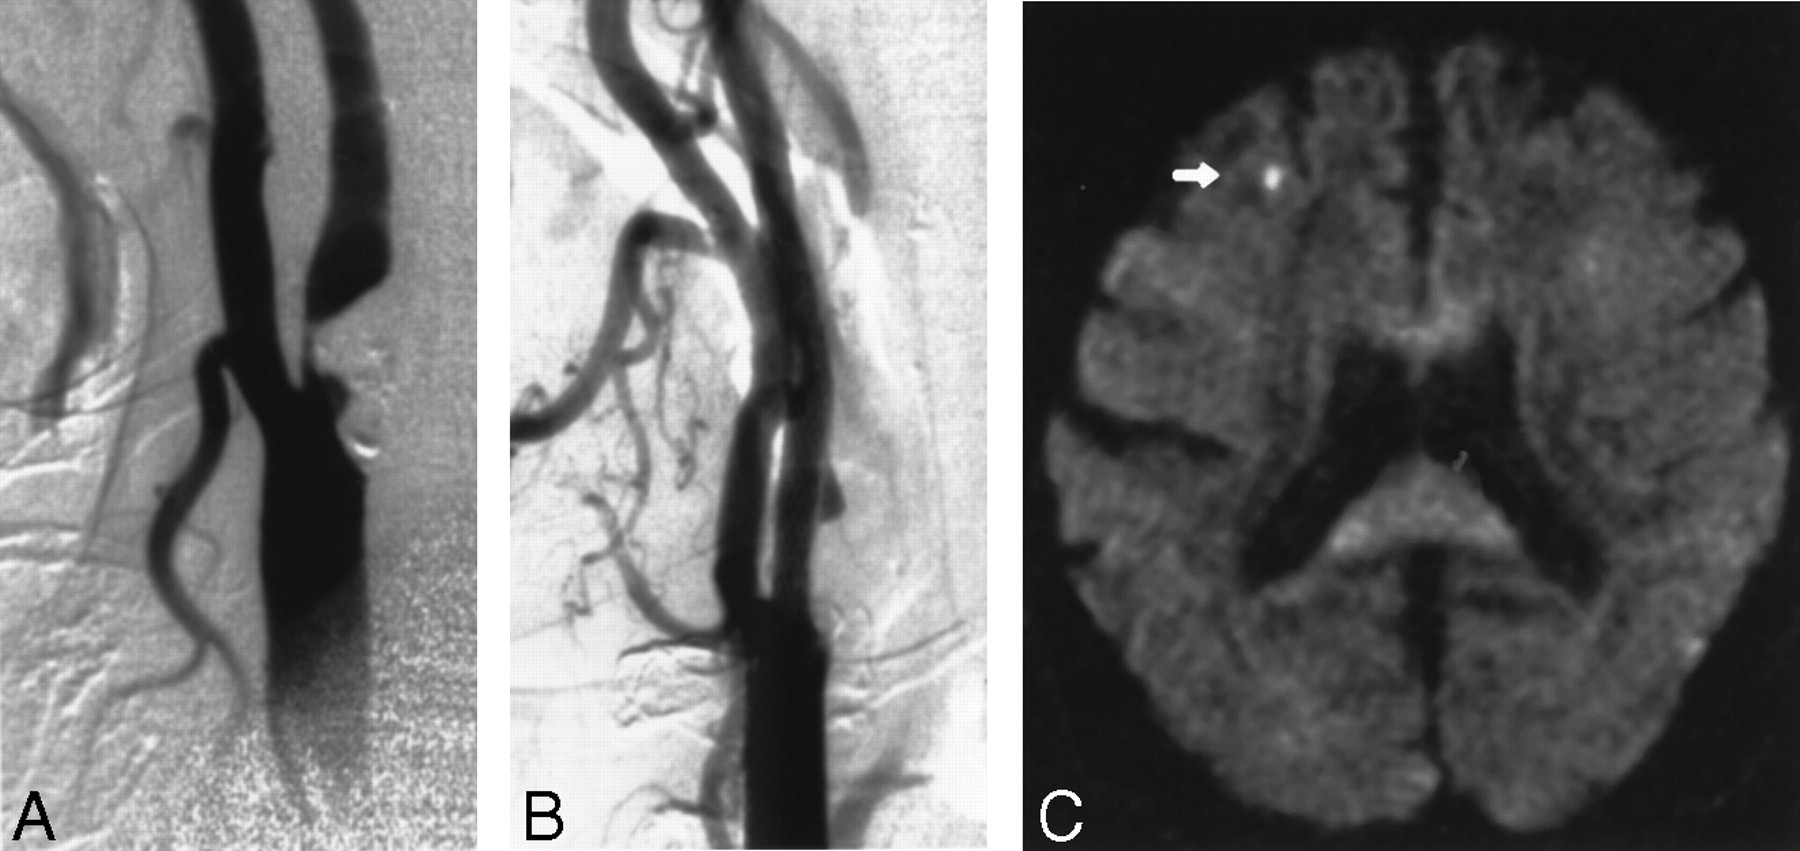

Images obtained in a 70-year-old man with an asymptomatic stenosis of the carotid artery.

A, Right anterior oblique angiogram shows a 94% stenosis of the right ICA.

B, Right anterior oblique angiogram shows the result after stent implantation.

C, Postprocedural axial diffusion-weighted MR image (6000/103/1) shows a new ipsilateral lesion (<5 mm) in the cortical territory of the MCA (arrow).